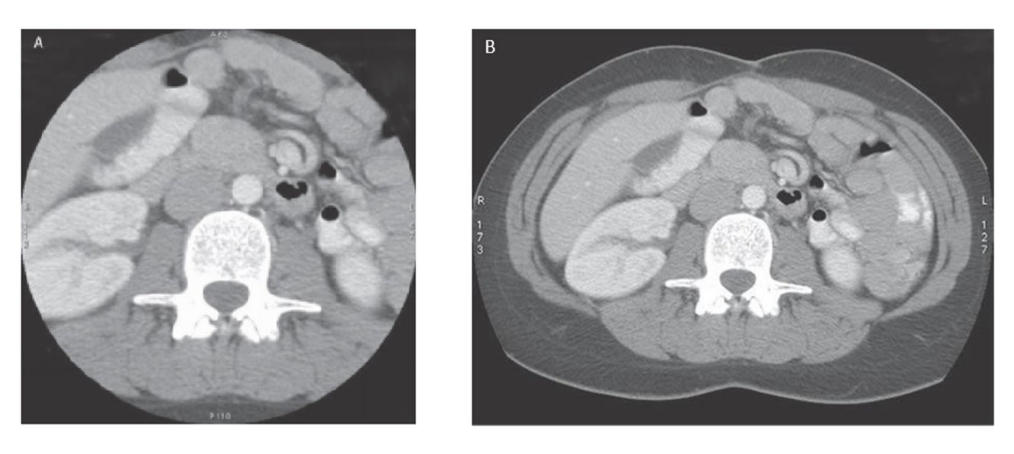

What is happening in this image

A

retrospective recon of DFOV